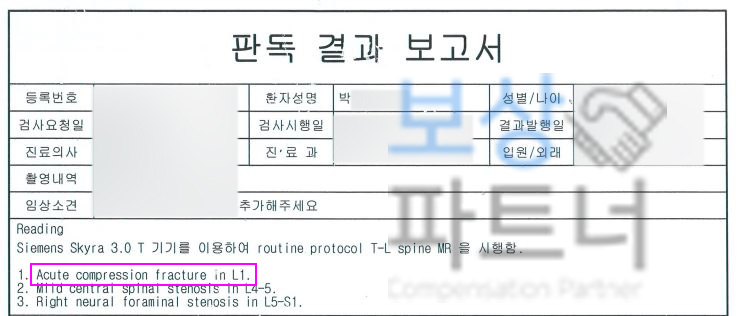

보상파트너로 문의해주셨던 서울시 거주 박@@님 또한 무거운 책을 드시다가 허리를 삐끗하셨다고 했는데요, 계속된 통증에 병원에 내원하여 Mri 등 정밀 검사를 받으셨고 진단 결과

L1 척추 요추압박골절

S32020 진단받으셨습니다. 박@@님은 수상일로부터 약 8주간 TLSO 허리보조기 착용하며 비수술 보존치료 진행하셨는데요, 장해보험금 청구를 위해서는

영상CD 및 영상판독지를 보면 Acute compression fracture in L1 **급성 요추압박골절 **확인됩니다. 보상파트너는 보험사도 인정할 공신력있는 상급병원 전문의로부터 후유장해 평가 받았고